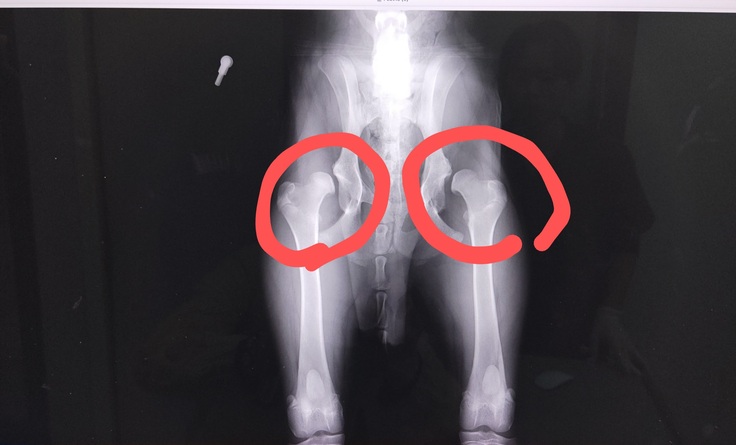

予防注射の際に動物病院で相談し、レントゲン検査を受けたところ、両足ともに股関節形成不全であることが判明しました。

定期検査で動物病院へ行くと、東京から外科専門の獣医師が来ており、診ていただくと、すでに脱臼していると診断されました。

この状態では、予防的な処置は難しく、マーロウに残された選択肢は、救済手術の骨頭切除か、治療手術の人工関節全置換術のどちらかと説明を受けました。

定期検査に連れて行き、レントゲンを撮りました。結果は以前と変わらず、関節は脱臼したままでした。獣医師からはそろそろ手術を受けられる月齢に達して来たことを伝えられました。

レントゲン検査の結果、前回から大きな変化は見られず、現状を維持している状態でした。